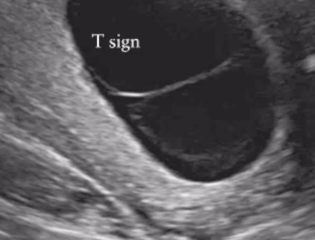

what is the T sign indicative of

single placenta

MCDA twins